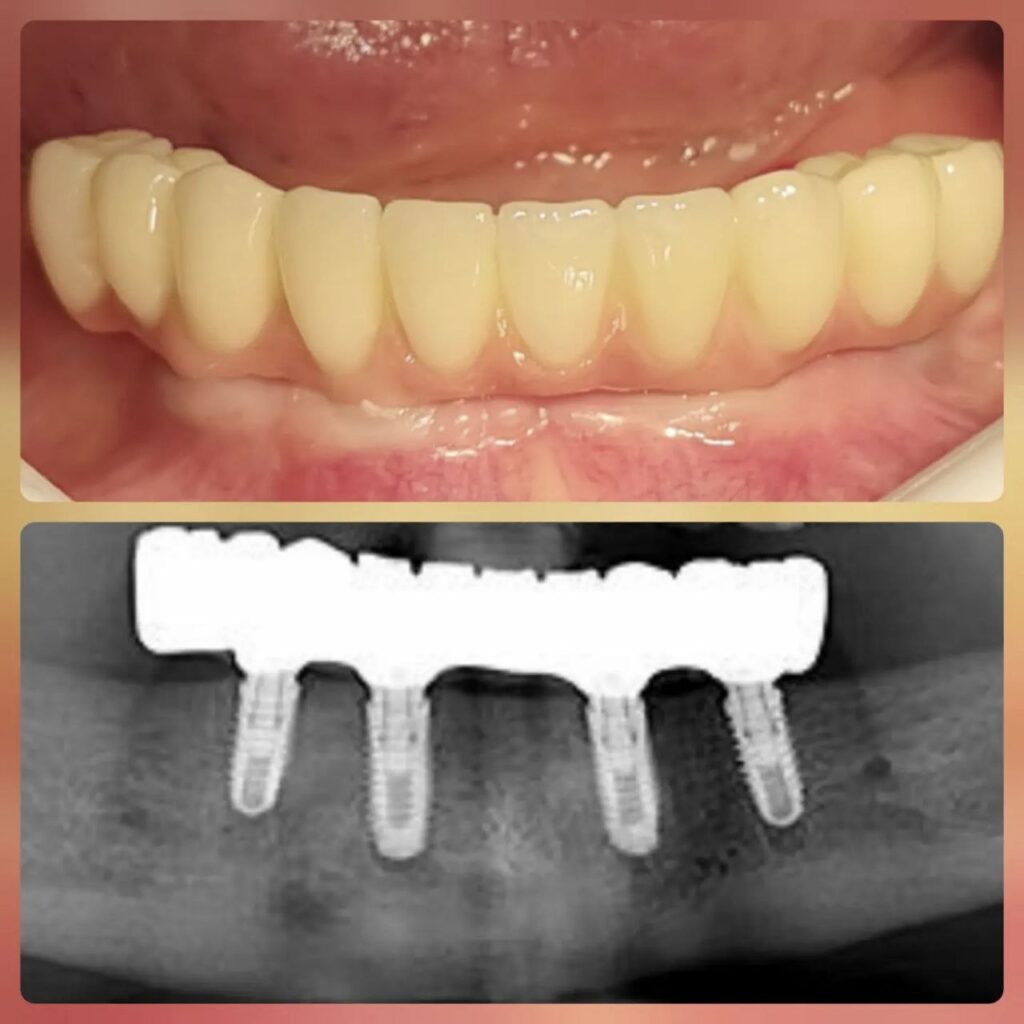

کاشت ایمپلنت دندان

اطمینان حاصل کردن از اینکه دندانهایتان به نحوی زیبا و طبیعی جایگزین شدهاند، از اهمیت بسیاری برخوردار است. ایمپلنت دندان به عنوان یک روش درمانی دائمی در دندانپزشکی شناخته میشود که حاصل آن، یک دندان زیبا و طبیعی در دهان شما خواهد بود.

هرچند که این روش درمانی هزینهی بیشتری نسبت به روشهای دیگر دارد، اما ارزش زیبایی که ایجاد میکند، قابل انکار نیست. ایمپلنتها به قدری شبیه به دندانهای طبیعی هستند که به سختی میتوان آنها را از دیگر دندانها تشخیص داد.